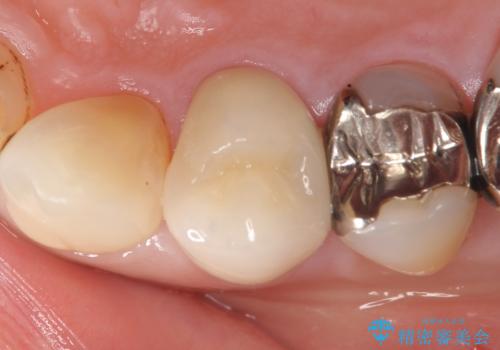

- 右上4番目の歯がなにもしなくてもズキズキ痛むといらっしゃった方の症例です。

検査の結果持続痛も認めたため、虫歯除去後根管治療を行いました。

その後オールセラミッククラウン(エクセレント)による補綴を行いました。